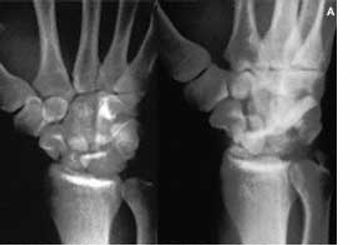

A 22-year-old soldier's left hand, wrist, and distal forearm were crushed by an object that weighed 90.8 kg (200 lb). There were no signs of open fracture; soft-tissue injuries were obvious. No neurovascular deficit was discerned in the limb.

A 24-year-old man sustained a fall on his outstretched hand (FOOSH) injury that was complicated by wrist hyperextension. He complained of persistent right wrist pain and loss of grip strength.